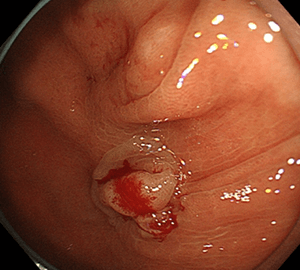

内視鏡的粘膜切除術(EMR)

比較的大きめの大腸ポリープや平坦な病変などの切除の際に行います。

1:ポリープを見つけ、NBI併用拡大観察をした後…1:ポリープを見つけ、NBI併用拡大観察をした後…

2:ポリープ直下の粘膜下層に局注液を注入します。2:ポリープ直下の粘膜下層に局注液を注入します。

3:ポリープをスネアに通し、周囲の正常粘膜を入れて病変を絞扼し…3:ポリープをスネアに通し、周囲の正常粘膜を入れて病変を絞扼し…

4:通電して切除し、周囲を観察して病変の遺残がないことを確認します。4:通電して切除し、周囲を観察して病変の遺残がないことを確認します。

5:切除面をクリップで縫合閉鎖し、回収した検体の病理検査を行います。5:切除面をクリップで縫合閉鎖し、回収した検体の病理検査を行います。